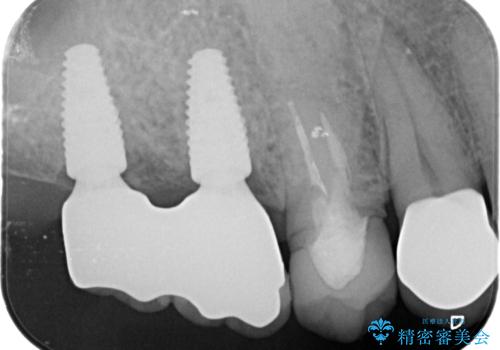

より清掃性の高い、チタン製カスタムアバットメント、審美製・強度に優れるジルコニアインプラントを用いたインプラント治療を計画します。

- 88万円(インプラント×2・チタンカスタムアバットメント×2・ジルコニアクラウン×2・仮歯×2)費用は治療当時の料金となります

天然の歯のようにしっかりと噛むことができるようになり、またしっかりと食事を楽しんでいただけるようになりました。